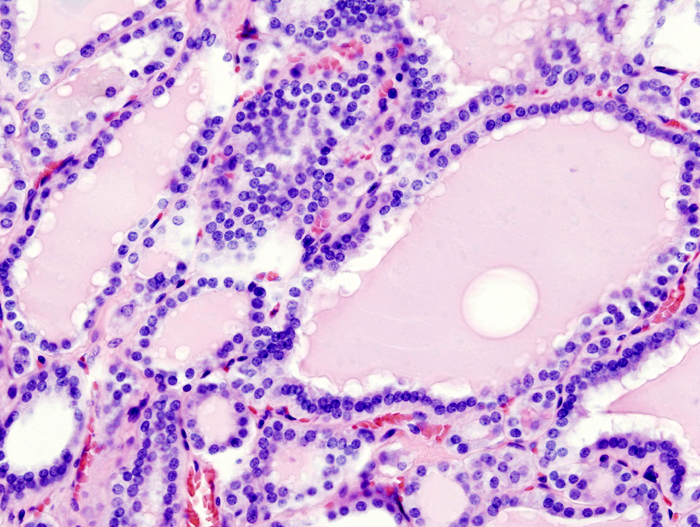

Hyperthyroidism

Hyperthyroidism_(1).jpg